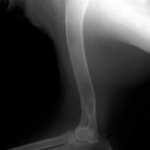

症例:トイプードル 9カ月齢

3ヵ月前より左前肢の跛行が認められるとのことで、来院されました。整形外科学的検査において、患肢の肘関節・肩関節重度の伸展制限が認められました。Xray検査において、左肩関節の内方脱臼、および肩甲骨関節窩の低形成と上腕骨頭の変形が認められました。

数か月に及ぶ慢性脱臼のため、関節面の低形成・摩耗のため整復手術による適切な再建は困難と判断し、切除関節形成術を実施しました。